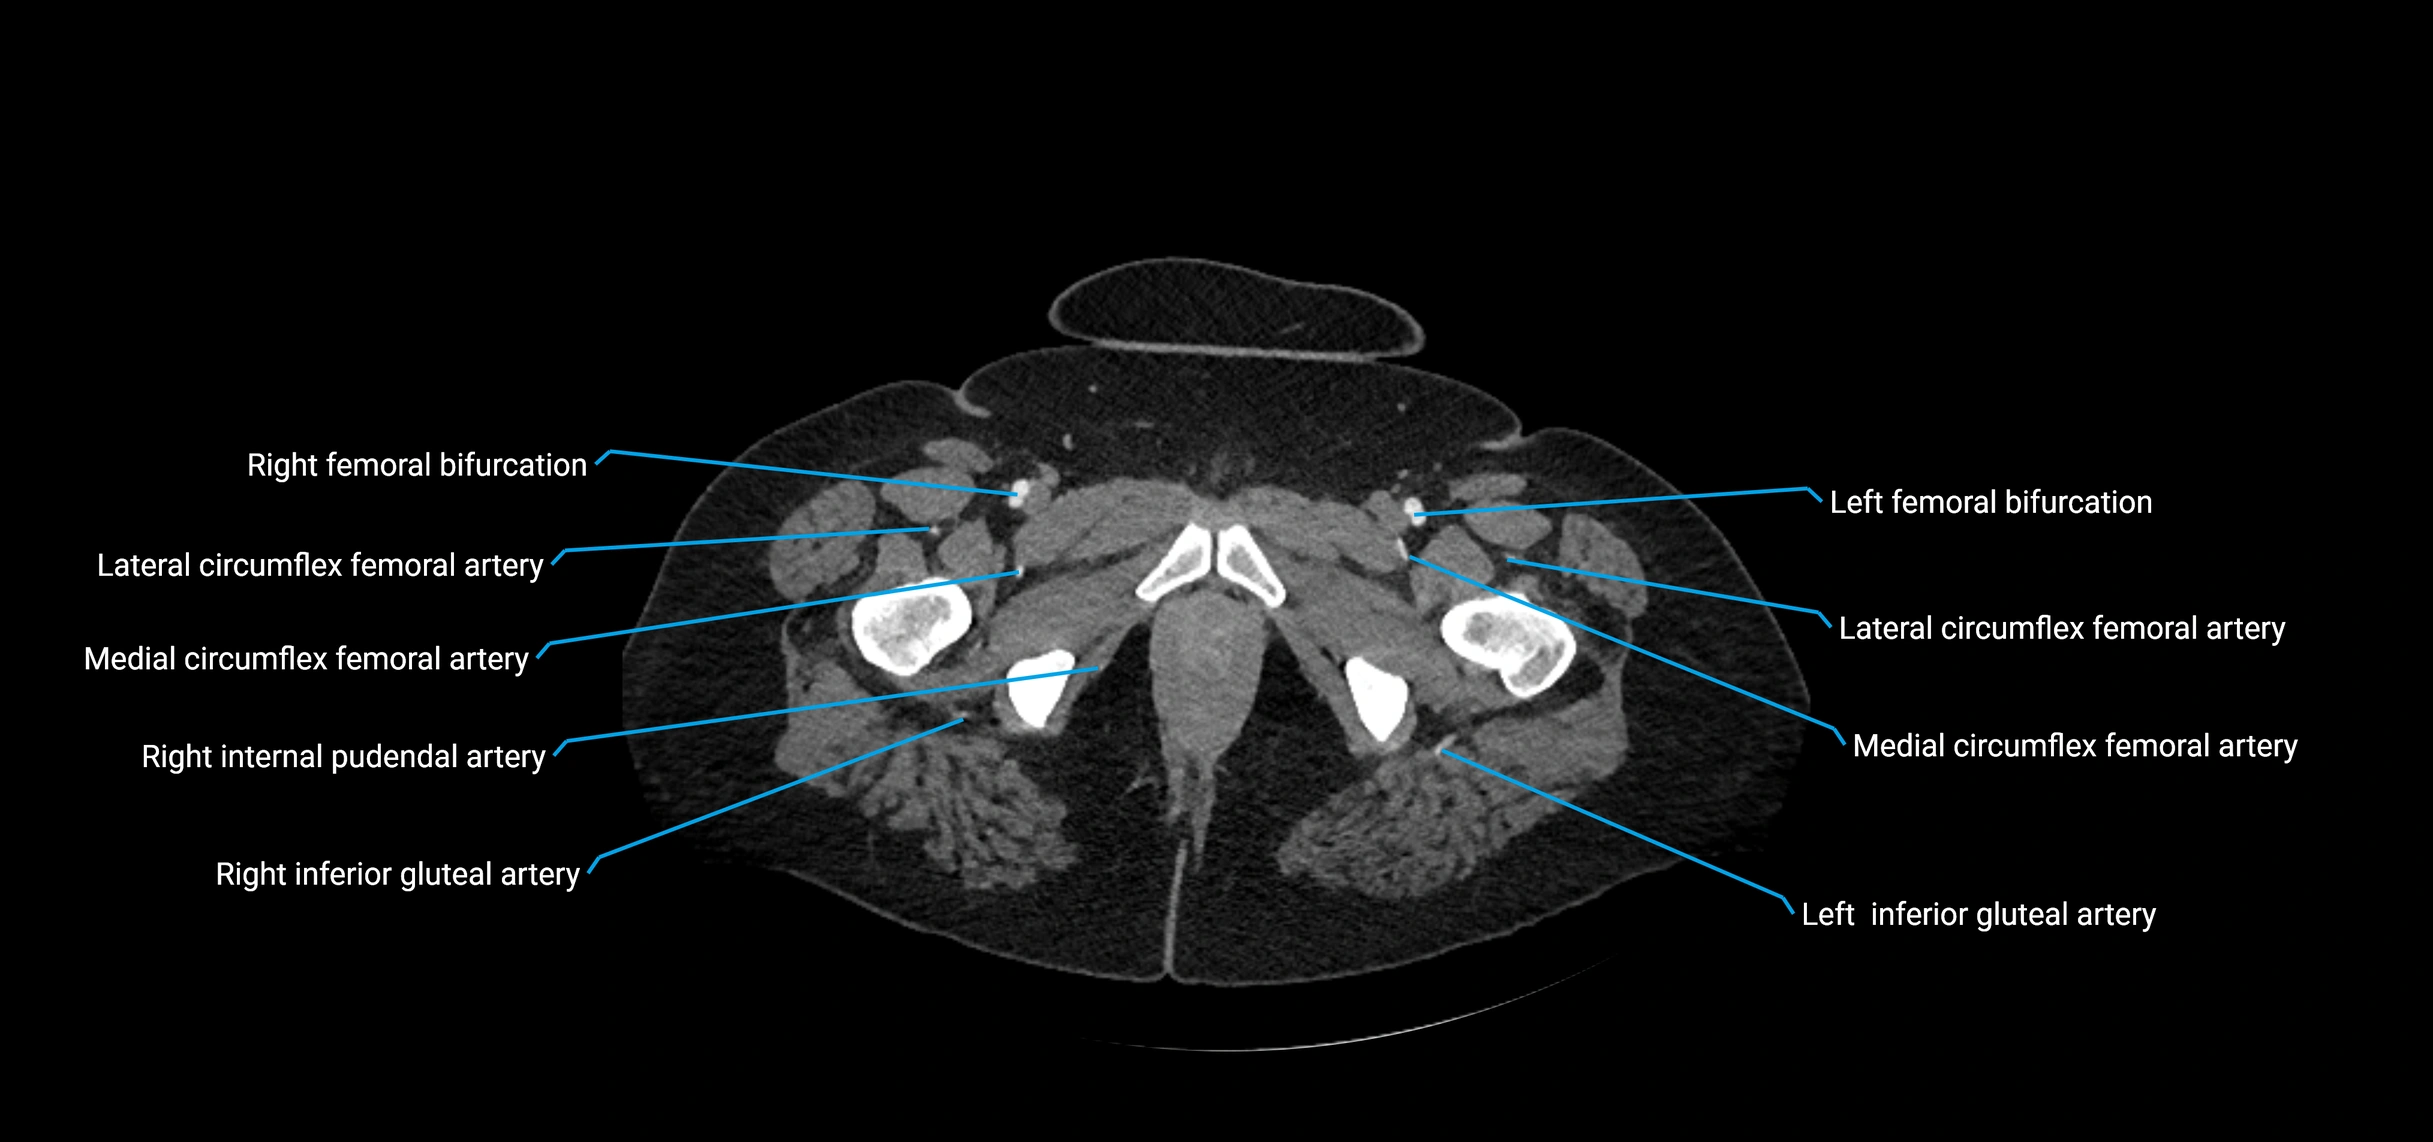

CT images

image

Contrast-enhanced CT (CTA):

• Gold standard for abdominal aortic imaging

• Provides excellent detail of lumen, wall, aneurysm, thrombus, and branch vessels

• Multiplanar and 3D reconstructions help in aneurysm measurement, stent graft planning, and dissection evaluation